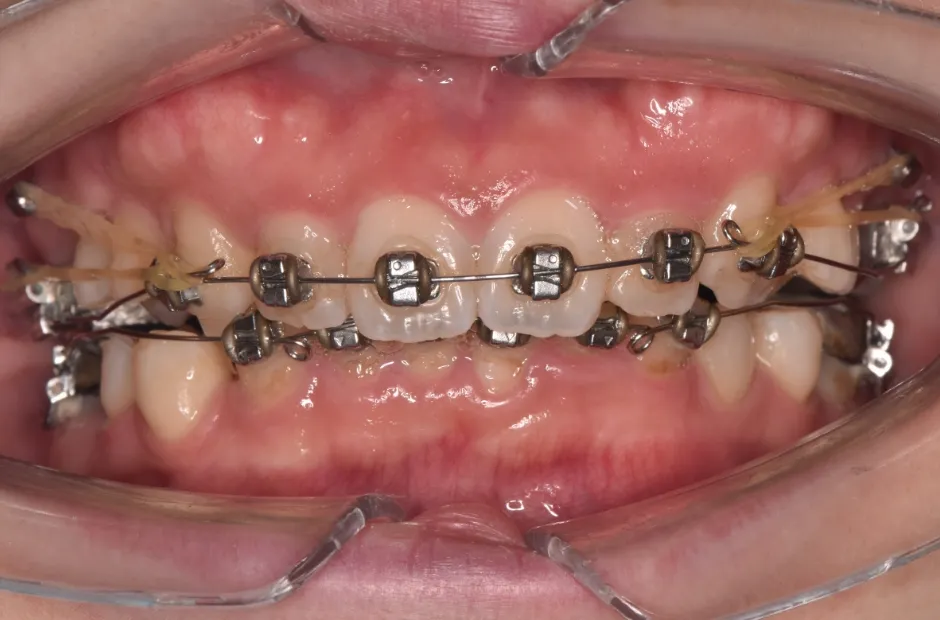

| 診断名・主訴 | 下顎前突、叢生 |

|---|---|

| 年齢・性別 | 23歳・女性 |

| 治療期間・回数 | 3年 |

| 治療に用いた主な装置 | 上顎5,5 下顎4,4 |

| 抜歯部位 | 舌側矯正 |

| 治療費 | 100万円(税抜) |

| リスク・副作用 | 装置による違和感・疼痛・歯肉退縮・歯根吸収・虫歯のリスクなど |

治療中